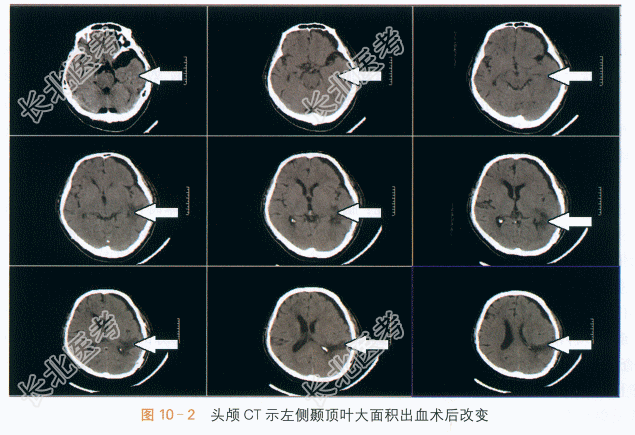

(2)头颅CT(术后):左侧颞顶叶脑出血术后复查,对比前片,高密度影基本消失,右侧基底节区腔隙灶,如图10-2所示。